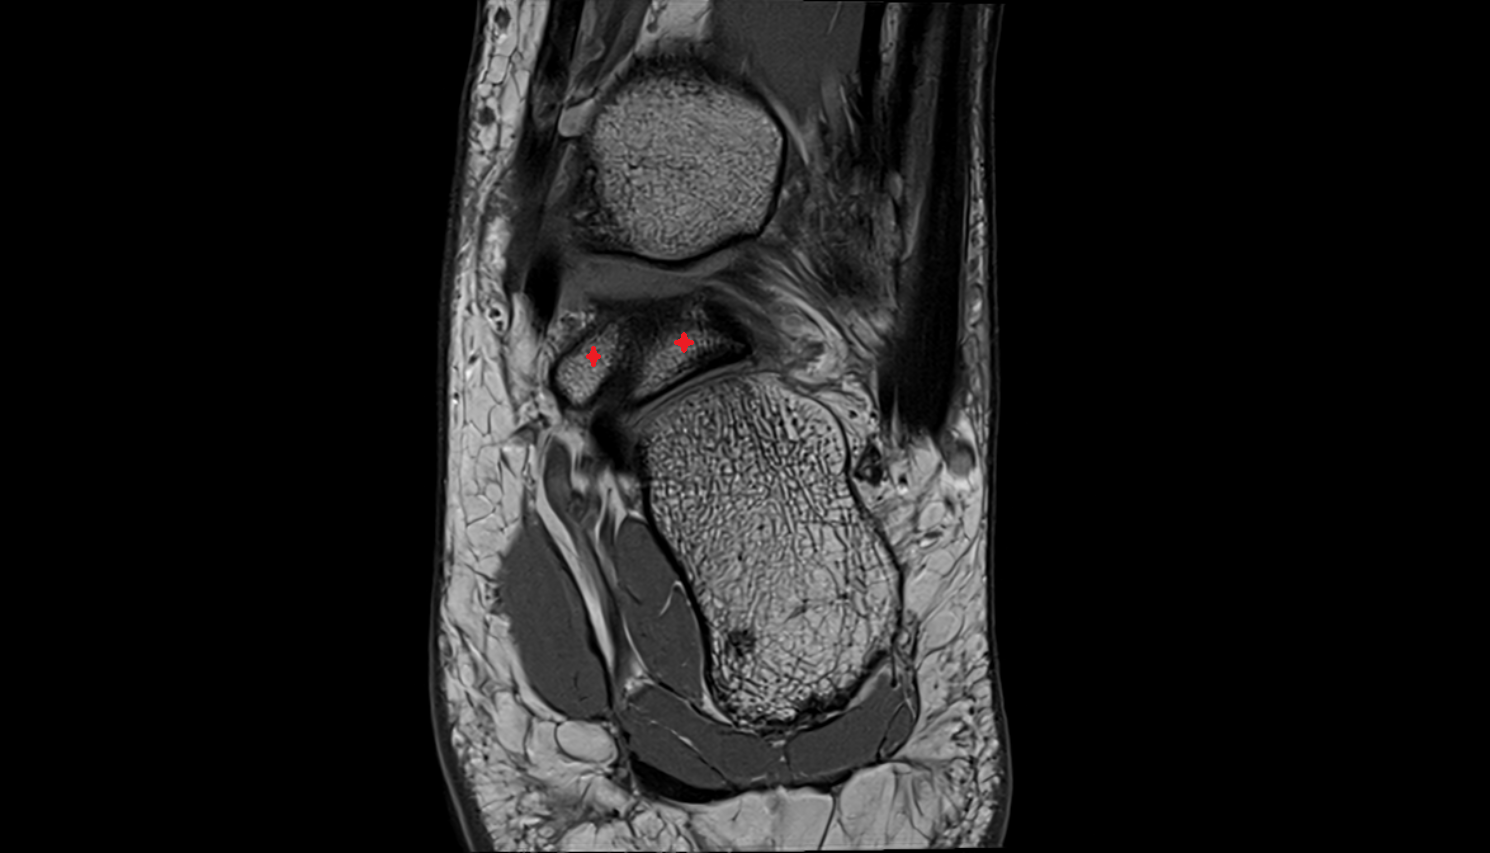

- Talus

- Head of talus

- Body of talus

- Neck of talus

- Calcaneus

- Sustentaculum tali

- Ankle joint

- Talocalcaneal joint

- Talocalcaneonavicular joint

- Tibialis posterior tendon

- Achilles tendon